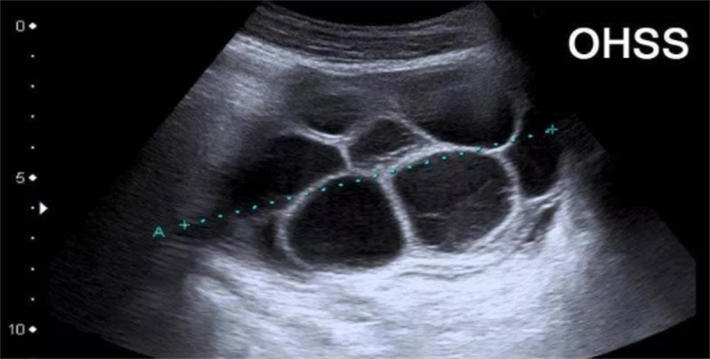

促排卵环节作为试管周期的关键一步,承载着培育优质卵子的希望,但同时也潜藏着一个不容忽视的风险——卵巢过度刺激综合征(OHSS)。当检查报告上出现“E2过高”“卵泡过多”的字样,正是身体发出的预警信号,而科学、精准的监测,就是守护试管安全、规避OHSS风险的核心预警系统。

卵泡过多则是OHSS的另一个重要预警信号。临床研究表明,当促排期间直径≥10mm的卵泡数量超过20个,或直径5-12mm的中小卵泡过多,就提示卵巢反应过强,发生OHSS的风险会显著升高。这类中小卵泡对OHSS的预测价值甚至高于直径>14mm的大卵泡,因为其数量过多会导致雌激素水平异常升高,进而引发血管通透性增加,为OHSS的发生埋下隐患。